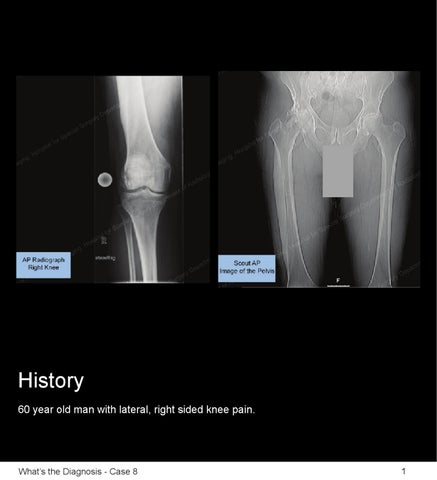

Hospital for Special Surgery is a world leader in orthopedics, rheumatology and rehabilitation. HSS is ranked #1 in the nation for orthopedics. Located in New York City.